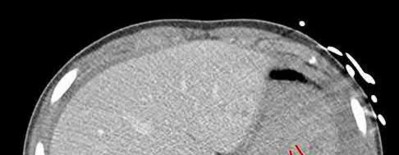

Question 12:

A 55-year-old patient presents with a slowly enlarging, painful mass in the proximal humerus. Biopsy reveals a hyaline cartilage matrix with cellular atypia, confirming a diagnosis of central conventional chondrosarcoma. Which of the following genetic mutations is most frequently identified in this specific tumor?

Correct Answer: IDH1 / IDH2

Explanation:

Mutations in the isocitrate dehydrogenase genes, IDH1 and IDH2, are found in up to 50-60% of central conventional chondrosarcomas and enchondromas. EXT1 and EXT2 mutations are characteristic of multiple hereditary exostoses (osteochondromas). GNAS mutations are seen in fibrous dysplasia. TP53 and RB1 mutations are hallmark aberrations in osteosarcoma.